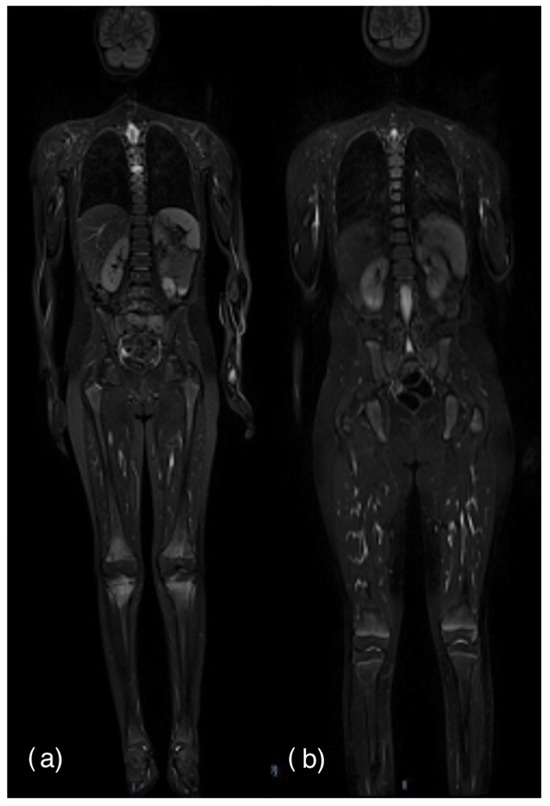

2.2. Imaging

- Zadig, P.; von Brandis, E.; Lein, R.K.; Rosendahl, K.; Avenarius, D.; Ording Müller, L.S. Whole-body magnetic resonance imaging in children—How and why? A systematic review. Pediatr. Radiol. 2021, 51, 14–24. [Google Scholar] [CrossRef]

- Zadig, P.; Von Brandis, E.; d’Angelo, P.; de Horatio, L.T.; Ording-Müller, L.-S.; Rosendahl, K.; Avenarius, D. Whole-body MRI in children aged 6–18 years. Reliability of identifying and grading high signal intensity changes within bone marrow. Pediatr. Radiol. 2022, 52, 1272–1282. [Google Scholar] [CrossRef] [PubMed]

- Von Brandis, E.; Zadig, P.K.; Avenarius, D.F.M.; Flatø, B.; Knudsen, P.K.; Lilleby, V.; Nguyen, B.; Rosendahl, K.; Müller, L.-S.O. Whole body magnetic resonance imaging in healthy children and adolescents. Bone marrow appearances of the axial skeleton. Eur. J. Radiol. 2022, 154, 110425. [Google Scholar] [CrossRef] [PubMed]